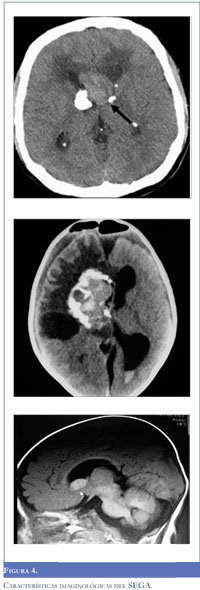

Diversos estudios de asociación genómica han encontrado que el riesgo familiar para el desarrollo de gliomas relacionados a síndromes familiares está circunscrito entre tres y cinco regiones cromosómi-cas; a partir del análisis de dos estudios de casos y controles que incluyó más de 20.300 pacientes con tumores de estirpe glial, se documentó un incremento del 70% en el riesgo de desarrollar este tipo de neoplasias entre las familias comprometidas (29). Adriaensen y colaboradores, describieron a partir de un estudio de corte transversal que incluyó 285 pacientes con TSC la evidencia tomográfica de SEGAs en el 20% de los casos, sin que hubiere diferencias significativas entre los dos sexos. Al momento del diagnóstico, el diámetro promedio de las lesiones fue de 11.4 milímetros (rango, 4-29 mm), la mediana para la edad de presentación fue de 31 años y el 21% tenía lesiones bilaterales. De igual forma, en el 14% de los casos se documentó hidrocefalia, y el acumulado para estimar el riesgo de encontrar una lesión glial de bajo grado favoreció la realización periódica (cada 3-6 meses) de resonancia magnética cerebral (RR 0.16, IC 95% 0.12-0.21) (Figura 4) (30). A partir de la revisión de los criterios diagnósticos para TSC realizada en 1998, se contempló la presencia de SEGAs aislados sin otras manifestaciones clínicas del complejo genético. Estos casos se consideran formas frustradas de TSC relacionadas con mosaicismo somático (19).

El compromiso cerebral en los pacientes con TSC consiste en la presencia de tuberomas corticales, heterotopias de la sustancia blanca, nódulos subependimarios y los SEGAs. La patogénesis común de estas alteraciones se asocia con el desarrollo cortical alterado por la migración y diferenciación anormal de las células embriónicas localizadas en la región sub-ventricular (31,32). La gran mayoría de los SEGAs se acompañan de otros nódulos subependimarios que no exhiben de forma constitutiva la pérdida de heterocigocidad ni la autofosforilación protéica de la vía mTOR (46% de los SEGAs y 14% de los tuberomas) (33). Desde la perspectiva clínica, la distinción entre los nódulos no neoplásicos y los SEGAs es importante debido a la influencia sobre las intervenciones terapéuticas relacionadas con el lento crecimiento de las lesiones tuberosas. Por el momento, los criterios imagenológicos para valorar el potencial tumoral de un nódulo subependimario son variables, en especial, debido a la mínima captación del contraste documentada en esta entidad. Son criterios relativos para definir la necesidad de cirugía o intervención con everolimus el tamaño tumoral, la localización de la lesión y su potencial para obstruir el drenaje normal del líquido cefalorraquídeo, la intensidad de señal en las secuencias T1 y la velocidad de crecimiento (Tabla 2).